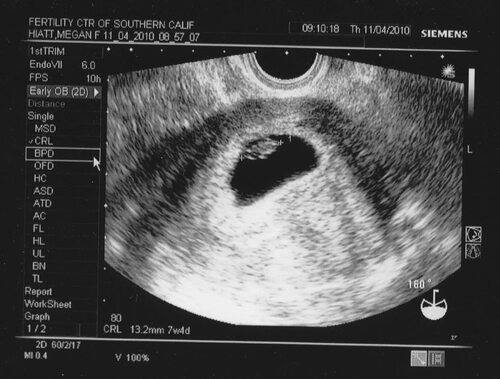

На 7 акушерских неделях беременности плод продолжает активно расти и формироваться. Фотографии узи в этот период могут показать уже сформировавшиеся основные органы и системы плода, такие как сердце, печень, почки и другие.

Фотографии узи на 7 акушерских неделях могут помочь врачам и будущим родителям отслеживать развитие плода, выявлять возможные аномалии и принимать необходимые меры. Также они могут стать важным воспоминанием для родителей после рождения ребенка.